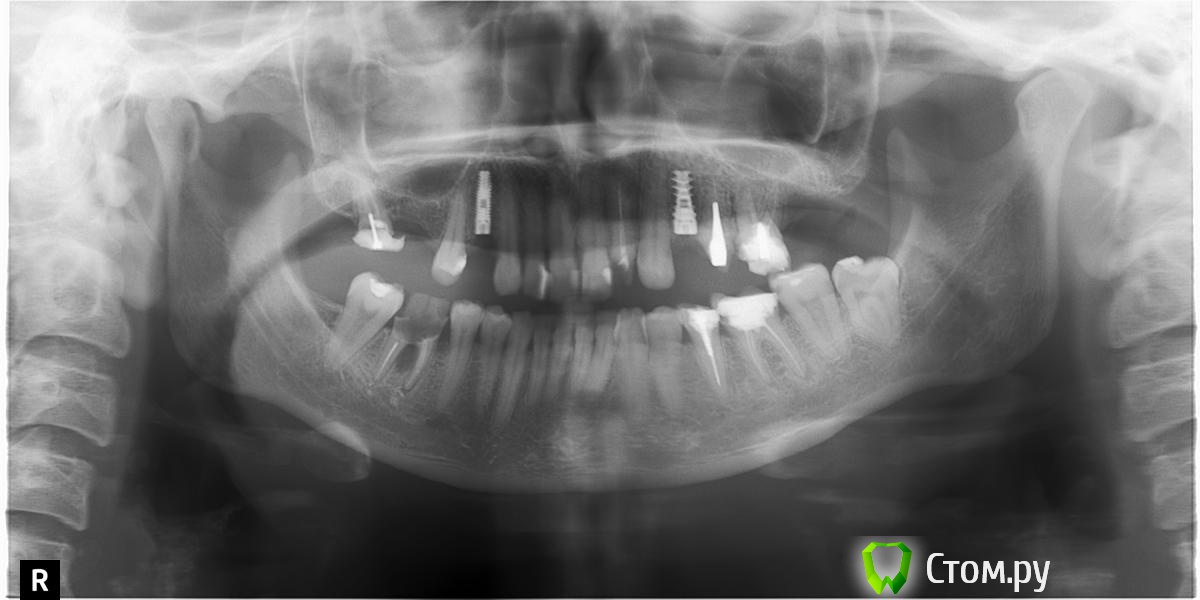

ILGAMSA Опубликовано 3 февраля, 2014 Автор Поделиться Опубликовано 3 февраля, 2014 задался этим вопросом около 6 мес назад делал подобные имплантации для сравнения.в абсолютно одинаковых условиях при заглублении на 0.5 мм Spi зарастает , у atid убыль ровно 1 мм.а я взаимосвязи с этим не вижу.http://s019.radikal.ru/i642/1402/83/88c28ba7b835.jpg 1 Ссылка на комментарий

RINAT05 Опубликовано 3 февраля, 2014 Поделиться Опубликовано 3 февраля, 2014 Возможно я слишком всматриваюсь но в этой ситуации наблюдал тоже самое только в области атида . Ссылка на комментарий

RINAT05 Опубликовано 3 февраля, 2014 Поделиться Опубликовано 3 февраля, 2014 Возможно я слишком всматриваюсь но в этой ситуации наблюдал тоже самое только в области атида .В области дистальных имплантатов справа хорошо видно образование кортикальной пластинки над spi и отсутствие над atid Ссылка на комментарий

kriokov Опубликовано 3 февраля, 2014 Поделиться Опубликовано 3 февраля, 2014 В области дистальных имплантатов справа хорошо видно образование кортикальной пластинки над spi и отсутствие над atidНе фактскорее там сохраненная язычная кортикальная на панораме проецируетсяощутимой разницы по снимку не вижу, одинаково нормально с костью в 4 сегменте Ссылка на комментарий

RINAT05 Опубликовано 3 февраля, 2014 Поделиться Опубликовано 3 февраля, 2014 (изменено) Не фактскорее там сохраненная язычная кортикальная на панораме проецируетсяощутимой разницы по снимку не вижу, одинаково нормально с костью в 4 сегментефакт, когда открыл имплантаты в Spi видно только шестиграник в заглушке остальное под костью, в 3 м сегменте заглушки все вровень с костью , открыты. Изменено 3 февраля, 2014 пользователем RINAT05 Ссылка на комментарий